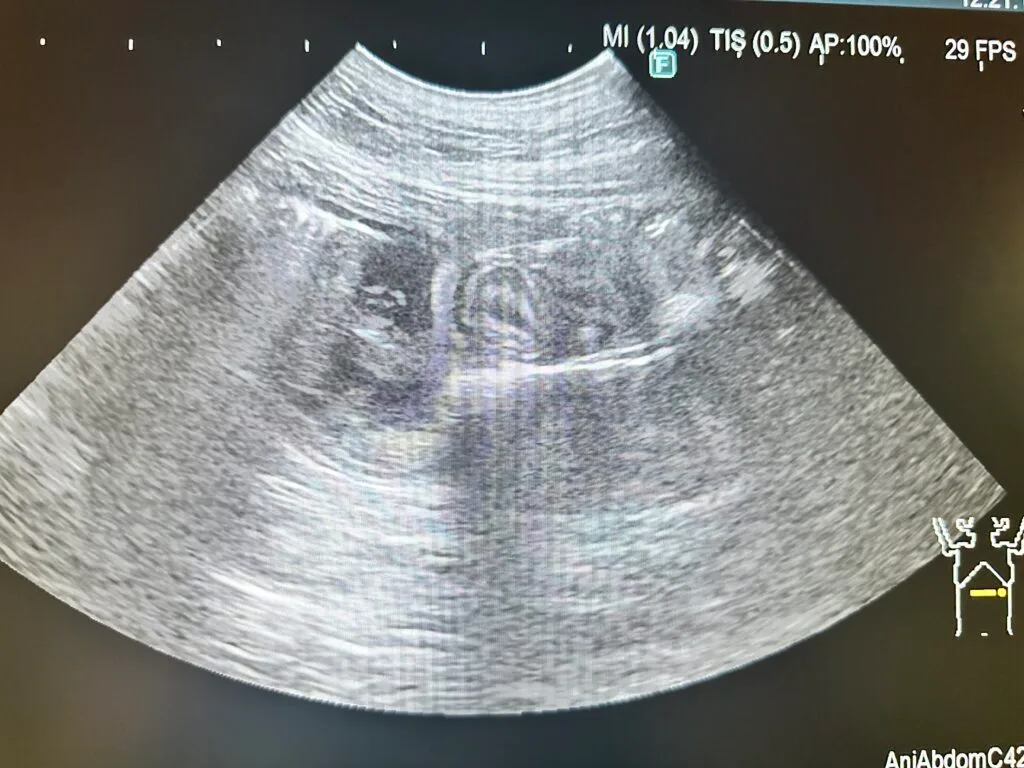

今回の症例の超音波画像です。

腸液の貯留と、その先にひも状の異物があり、腸がぐねぐねと蛇腹のようになっている様子が観察されました。

超音波検査のデメリットは、閉塞直後だと腸液の貯留が認められず閉塞が分かりづらい可能性があることと、検査者の技術によって診断精度に大きな差が出てしまうことが挙げられます。